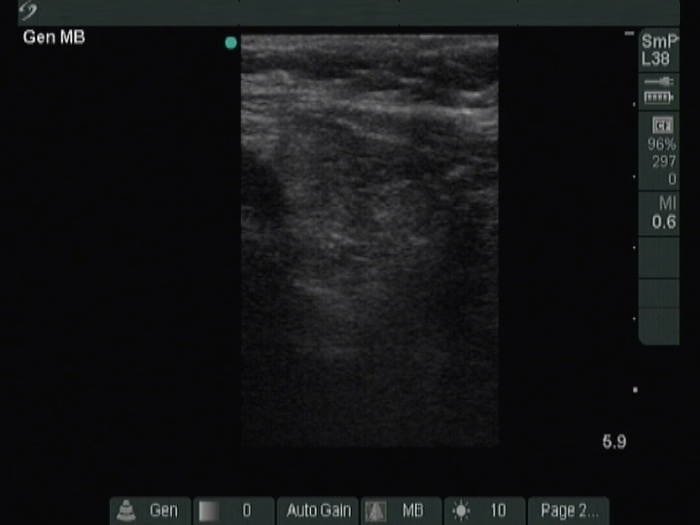

Right lobe, longitudinal scan

Left lobe, transverse view. The previously operated left lobe is moderately hypoechoic.